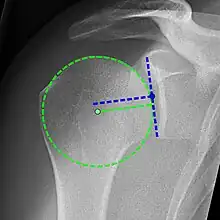

Xray

X-ray projectional radiography cannot directly reveal tears of the rotator cuff, a 'soft tissue', and consequently, normal X-rays cannot exclude a damaged cuff. However, indirect evidence of pathology may be seen in instances where one or more of the tendons have undergone degenerative calcification (calcific tendinitis). The humeral head may migrate upwards (high-riding humeral head) secondary to tears of the infraspinatus, or combined tears of the supraspinatus and infraspinatus.[47] The migration can be measured by the distance between:

- A line crossing the center of a line between the superior and inferior rims of the glenoid articular surface (blue in image).

- The center of a "best-fit" circle positioned over the humeral articular surface (green in image)

Normally, the former is positioned inferiorly to the latter, and a reversal is therefore indicating a rotator cuff tear.[47] Prolonged contact between a high-riding humeral head and the acromion above it, may lead to X-rays findings of wear on the humeral head and acromion and secondary degenerative arthritis of the glenohumeral joint (the ball and socket joint of the shoulder), called cuff arthropathy, may follow.[46] Incidental X-ray findings of bone spurs at the adjacent acromioclavicular joint may show a bone spur growing from the outer edge of the clavicle downwards towards the rotator cuff. Spurs may also be seen on the underside of the acromion, once thought to cause direct fraying of the rotator cuff from contact friction, a concept currently regarded as controversial.